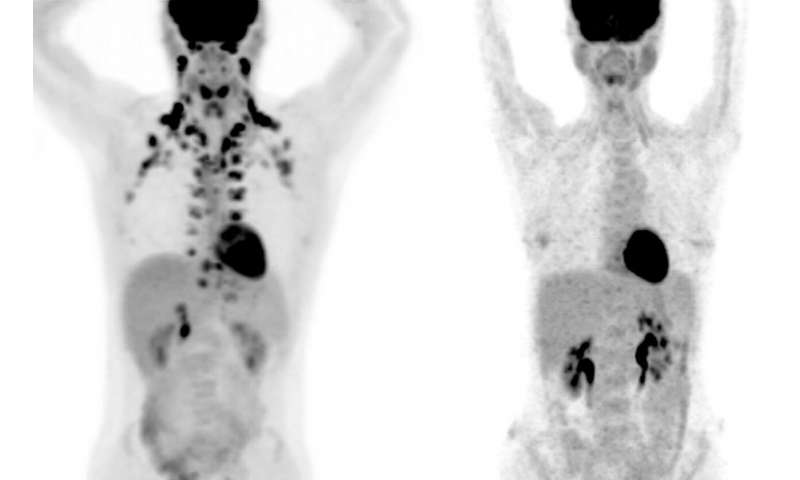

Large-scale studies of brown fat, however, have been practically impossible because this tissue shows up only on PET scans, a special type of medical imaging. “These scans are expensive, but more importantly, they use radiation,” says Tobias Becher, the study’s first author and formerly a Clinical Scholar in Cohen’s lab. “We don’t want to subject many healthy people to that.”

A physician-scientist, Becher came up with an alternative. Right across the street from his lab, many thousands of people visit Memorial Sloan Kettering Cancer Center each year to undergo PET scans for cancer evaluation. Becher knew that when radiologists detect brown fat on these scans, they routinely make note of it to make sure it is not mistaken for a tumor. “We realized this could be a valuable resource to get us started with looking at brown fat at a population scale,” Becher says.